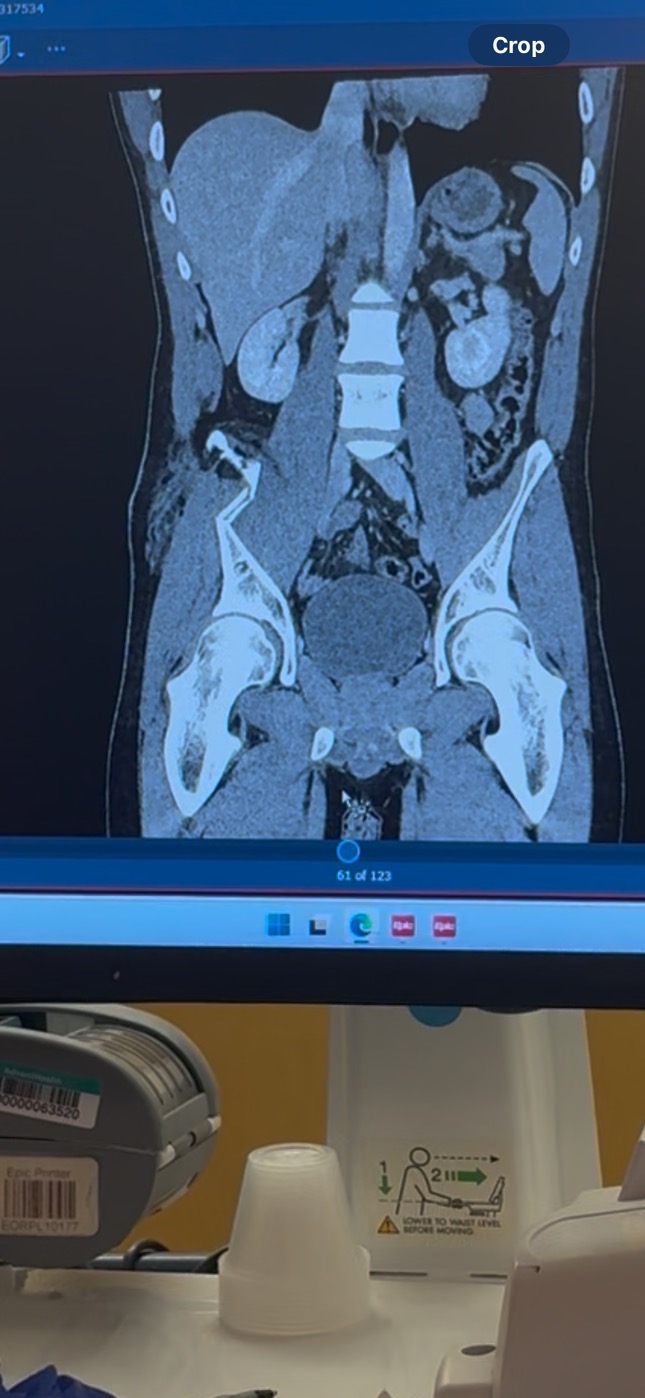

On October 4th, my boyfriend Emiliano Obregon had a serious work accident that left him with a broken hip. He needed surgery and will be unable to work for about 6 months.